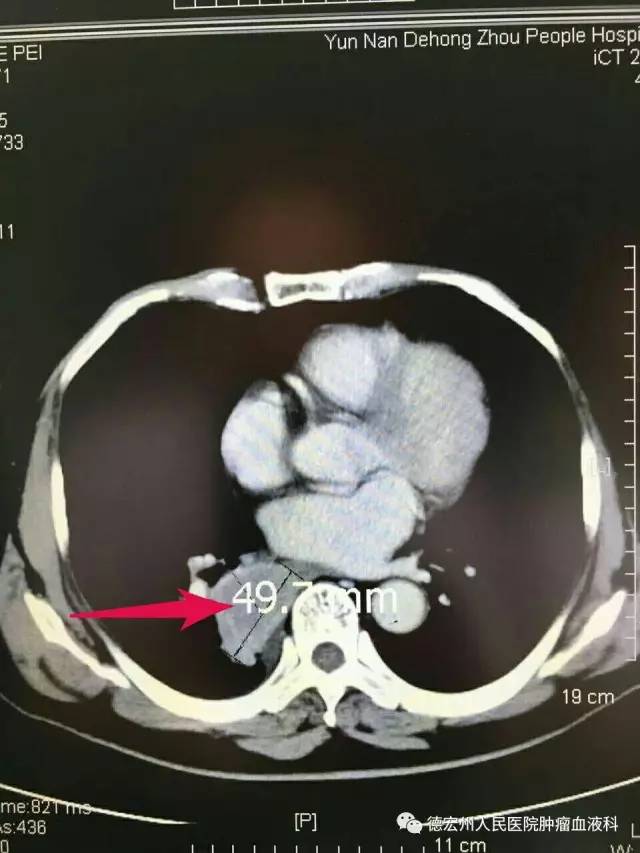

患者一,男,74岁,因乏力、纳差10余天于今年4月到州人民医院就诊,CT检查发现:患者右肺肿块。经CT引导下肺穿刺活检术,术后病理:右肺下叶鳞状细胞癌。患者确诊后转诊至省级医院,拟行外科手术治疗,但由于患者高龄,基础疾病较多(高血压、糖尿病、脑梗塞、肾功能不全等)不能耐受外科手术。于6月再次到州人民医院肿瘤血液科就诊,并于6月24日在CT引导下行经皮肺穿刺右下肺癌粒子植入手术治疗。 8月回院复诊时发现,其右下肺癌肿块消失。碘125粒子植入术又称体内伽玛刀,是肿瘤近距离放射治疗的一种,是治疗肿瘤的新手段。该项技术在局麻下完成,有创伤小、并发症少、术后恢复快等优点。从本患者的医治情况看,此技术疗效确切,获得满意的治疗效果。

① 术前右下肺约5cm肿块